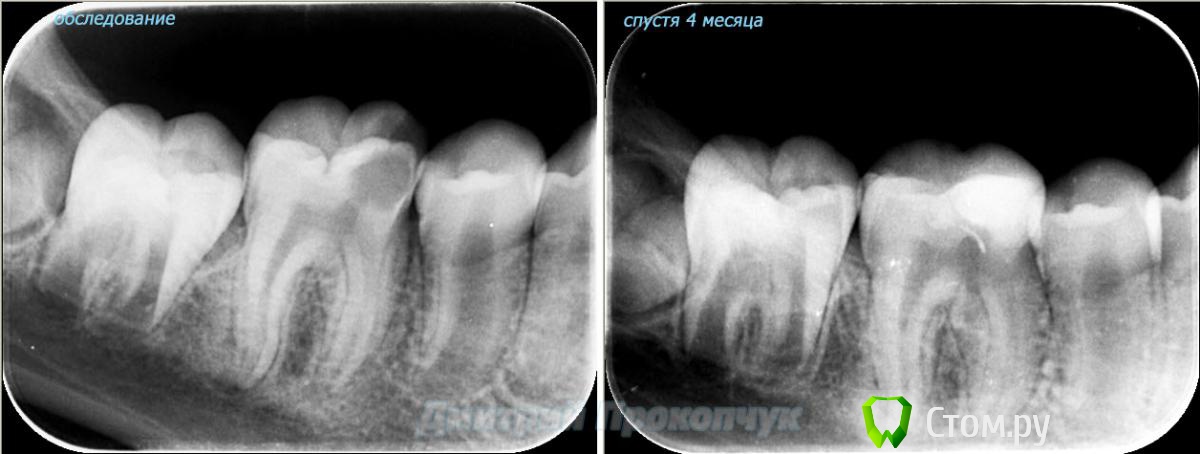

punkrat Опубликовано 16 сентября, 2014 Поделиться Опубликовано 16 сентября, 2014 Коллеги, тема , возможно, не имеет смысла просто приятная мне эндодонтия, сохранил с предыдущего места работы. Да, будь я проклят, я все знаю, НИГДЕ НЕТ КОФЕРА, на новом месте с этим норм. В общем если посчитаете, что я недостоин постить тут свои снимки, то так тому и быть, удалю тему.. 01. плановый ретрит 46ого и результат через 7 месяцев. Осложняющим моментом тут было то, что длина каналов была около 26 мм... 02. первичное эндо 34 (подготовка к ортопедии) + бонус - ретрит 35 03. ретрит 26 (подготовка к ортопедии) 04. ретрит 15, 16 (подготовка к ортопедии). основная сложность была в ретрите 15 - он был запломбирован термафилами, да еще снабжен свш... 05. ретрит 27 (подготовка к ортопедии). Ничего особенного, со временем посмотрим какова будет убыль этого совсем немаленького разрежения 06. ретрит 13. Разумеется пришлось выбивать вкладку, а потом еще попилить 3-4 миллиметра цемента, но, таки попилил куда нужно... 07. ретрит 17 (подготовка к ортопедии). В данном случае я, кажется, потратил больше времени на снятие литого моста, чем на лечение 17)) 08. ретрит 16 (подготовка к ортопедии). Снимка с инструментом нету, поскольку, визиограф сломался и его делал на пленку. 15 разумеется тоже перелечен... 09. плановый ретрит 16 10. первичное эндо 36, рядовой случай что дистальный щечный удалось найти не сразу, он был спрятан под нависающим дентиклем 11. ретрит 12, 11 (подготовка к ортопедии). Казалось бы, рядовой случай, если бы корневые каналы обоих зубов не были бы налухо забиты резорцин-формалиновой смесью... 12. ребенок 9ти лет, острый пульпит 46, попробовал оставить витальным. Пока полет нормальный, но даже если придется делать эндо в последствии, лучше когда оно будет сделано в более старшем возрасте... 13 Ссылка на комментарий

Л Ю С Я Опубликовано 17 сентября, 2014 Поделиться Опубликовано 17 сентября, 2014 Не люблю гутту на носителе. Как я только не извращалась, все равно неконтролируемый выход за апекс гутты или силера или недолет. Достаточно большие пафы. Некритично, но все же. Порадовал зуб ребенка, хорошо бы эндо избежать. На витальность проверяли? Ссылка на комментарий